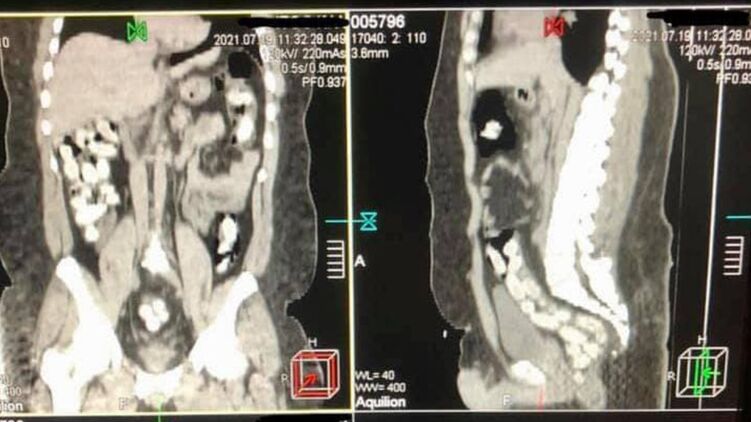

"В июле 2021 года в Борисполе был задержан бразилец, который в желудке ввез в Украину почти 1 кг кокаина. Мужчина проглотил 90 капсул, которые извлекали из кишечника медикаментозным путем после компьютерной томографии", - говорится в сообщении.

Напомним, 29-летний курьер с начиненными кокаином капсулами в желудке прибыл в аэропорт "Борисполь". Имея предварительную оперативную информацию, таможенники применили в отношении иностранца личный досмотр с привлечением медицинского работника. Процедура проходила в медицинском учреждении с применением компьютерной томографии брюшной полости мужчины.

Изъятие 90 капсул овальной формы, которые находились в его кишечнике, происходило медикаментозным путем и длилось почти три часа.